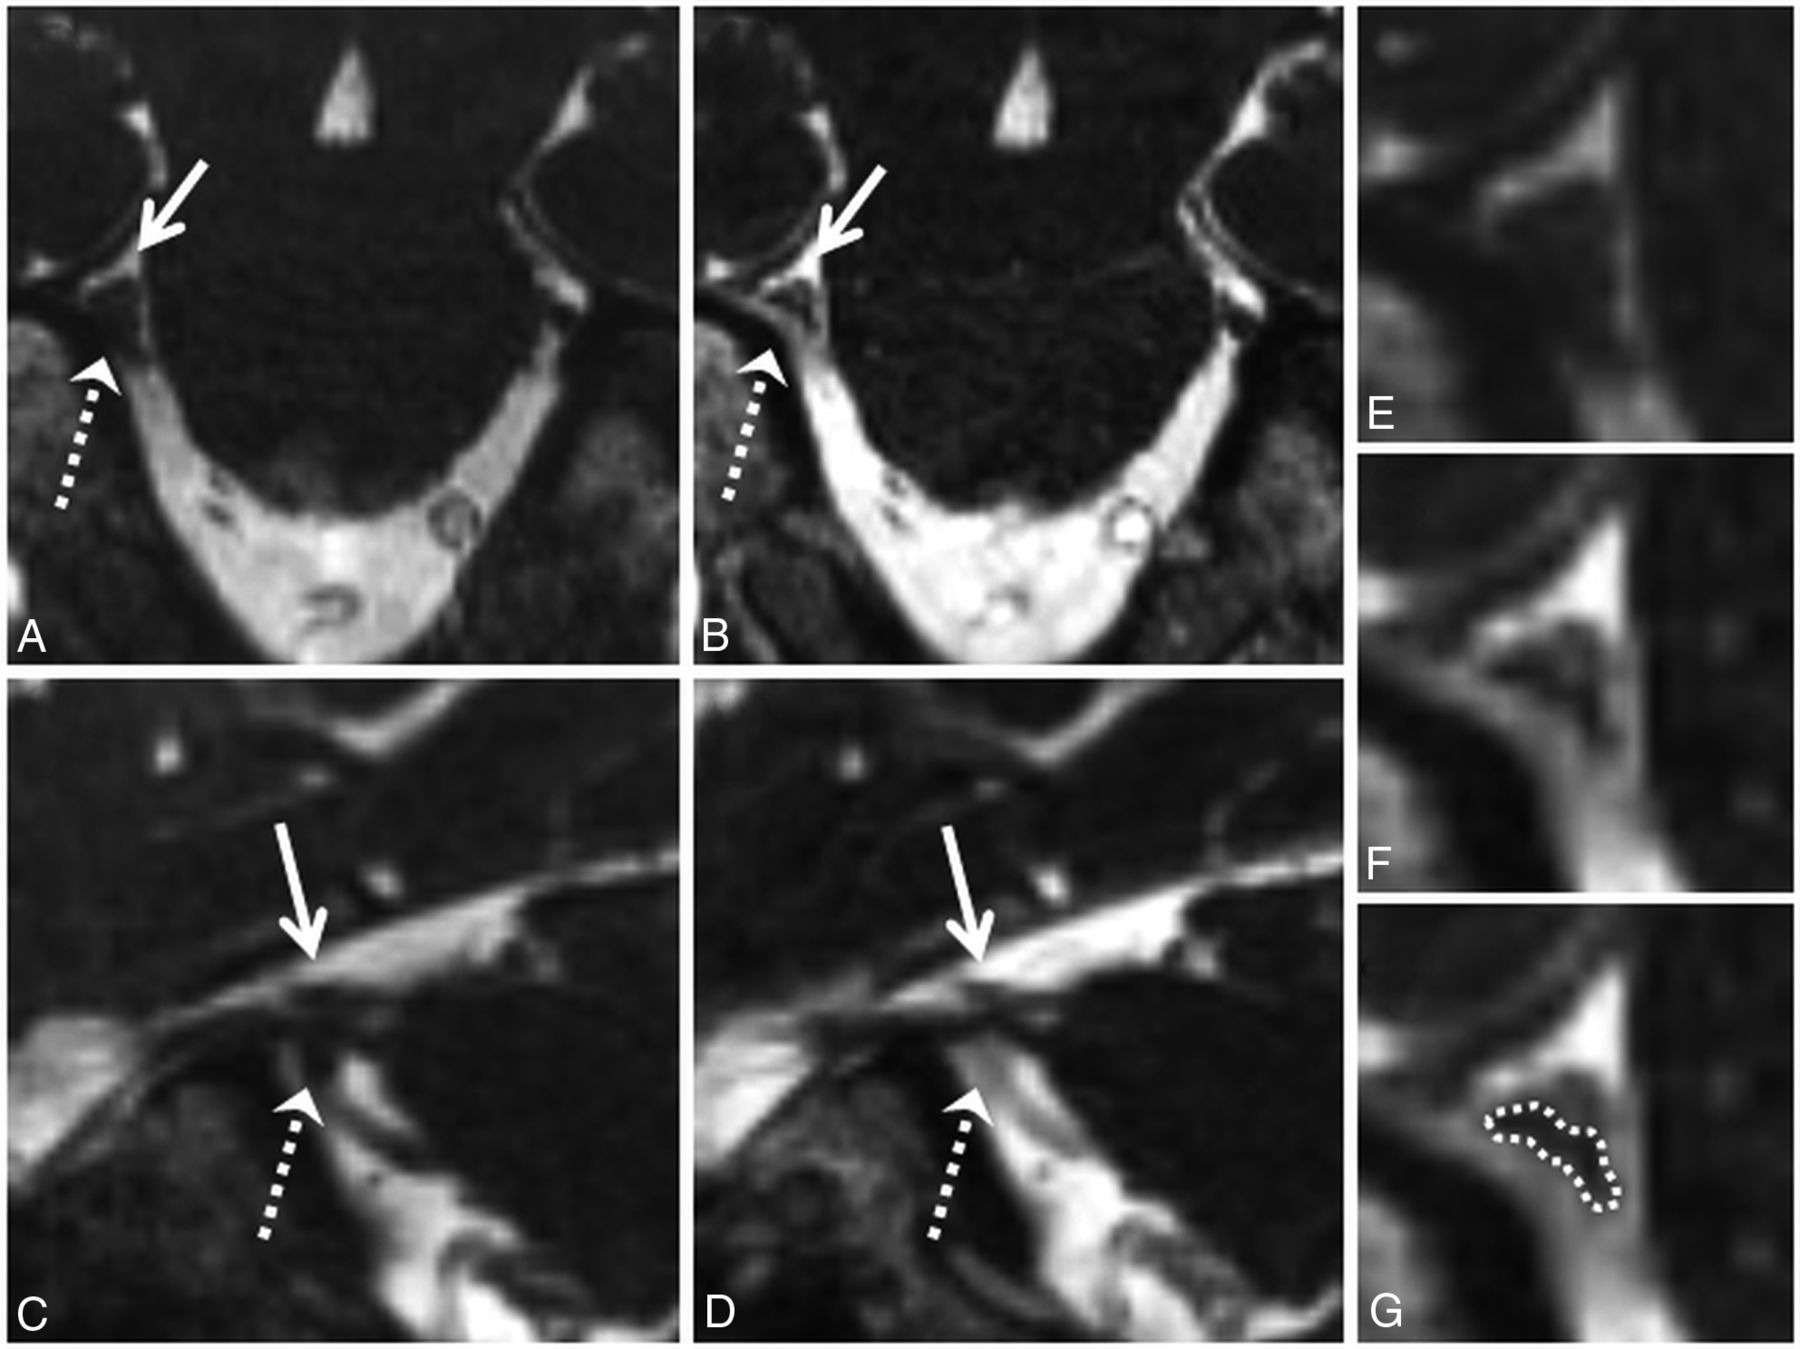

Grade 2 neurovascular conflict. Coronal NE-CISS (A) and CE-CISS (B) and sagittal NE-CISS (C) and CE-CISS (D) images show neurovascular conflict of the cisternal segment of the patient's right trigeminal nerve with a branch of the superior cerebellar artery from above (solid white arrow) and the superior petrosal vein from below (dashed white arrow), resulting in flattening of the nerve near the porus trigeminus. On the NE-CISS images (A and C), the nerve is not well-delineated from the adjacent vascular structures. On the CE-CISS images (B and D), the vessels enhance, outlining the compressed nerve between them. Zoomed-in images of the site of neurovascular conflict in the coronal plane (E and F) illustrate the poor contrast between vessels and nerve on the NE-CISS image (E) and the improved contrast after administration of gadolinium contrast material (F), allowing more confident delineation of the compressed nerve from the adjacent vessels (G). Both NE-CISS and CE-CISS images were interpreted as grade 2 compression. On the patient's left, grade 0 was given for both the NE-CISS and CE-CISS images.